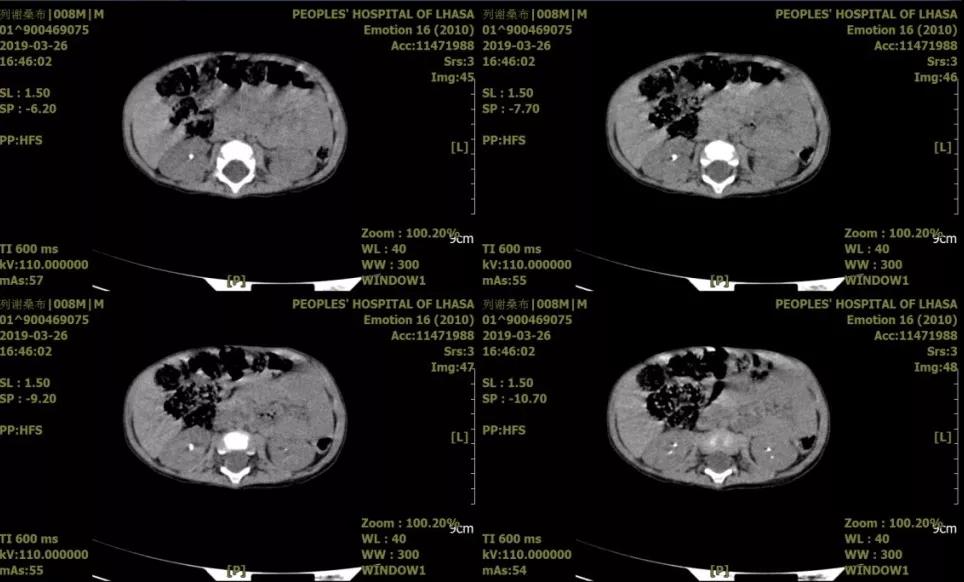

患儿,男,1岁10个月,主因“腹痛腹胀伴排尿困难1天”就诊。术前诊断:1.尿道结石;2.右输尿管结石;3.双肾结石。急诊一期予以经由尿道结石碎石术+右输尿管结石碎石术+双侧输尿管结石支架置入术。二期行mPCNL。